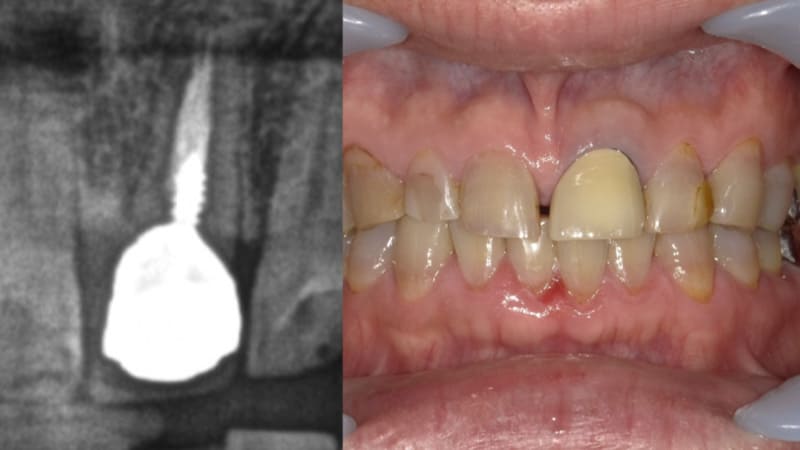

症例①:前歯が取れた

| 治療科目 | インプラント |

|---|---|

| 主訴 | 前歯が取れた |

| 治療期間 | 約半年 |

| 治療費 | 495,000円 |

| 治療内容 | 歯根破折していたため抜歯し3ヶ月待つ。インプラントガイドを使いフィクスチャー埋入。その後上部構造を装着した。 |

| 治療のリスク | インプラントが骨と結合しない場合撤去し、再度埋入が必要。噛み合わせに問題ある場合骨吸収を起こすためナイトガード装着をお願いすることがある。また定期的なメンテナンスで歯肉の炎症と咬合のチェックが必要。 |